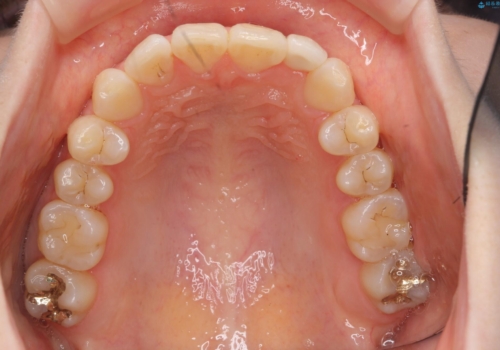

- 前歯の並びを主訴に来院。

マウスピースで歯を抜かずに治療しています。

左上の前歯が飛び出しており、唇が笑った時に引っかかっていたのが解消しています。

左上の前歯は小さいため、(矮小歯)左右対称になるようにセラミックで形を修正する治療も併用しています。

歯を大きくかぶせるスペースを作るため、右上の奥歯を後ろに下げています。

左にずれていた上の正中も揃い、大変喜んでいただきました。